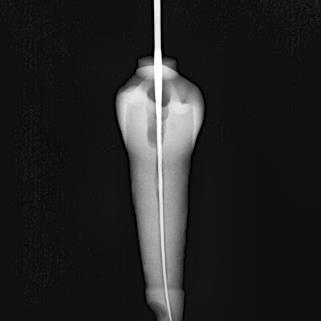

Conductometría real

Una vez que se realizó el acceso cameral de cada uno de los dientes, se procedióatomarunaradiografíaconunalima 15, finalmente se tomó una radiografía para determinar la conductometría real. (Figura 3)

Figura 3.

ConductometríarealdeOD#27

Fuente: Pérez V, Salinas L. 2022